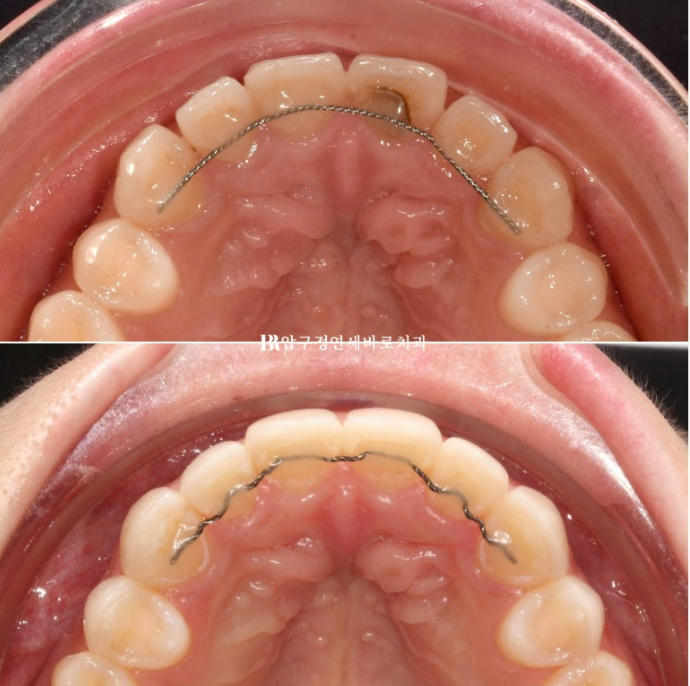

무삭제 라미네이트 젤라미 두께가 어느정도인지 가늠할 수 있도록 교합면 사진을 비교해보겠습니다.

위가 초진, 아래가 8개 치아 전부에 삭제 없이 무삭제 라미네이트를 부착한 모습입니다.

두께차이가 보이지 않는 정도라는 것은 젤라미의 두께가 어느정도로 얇은지 보여줍니다.

가장 얇은 곳 기준 0.1mm 까지 재현이 가능합니다.